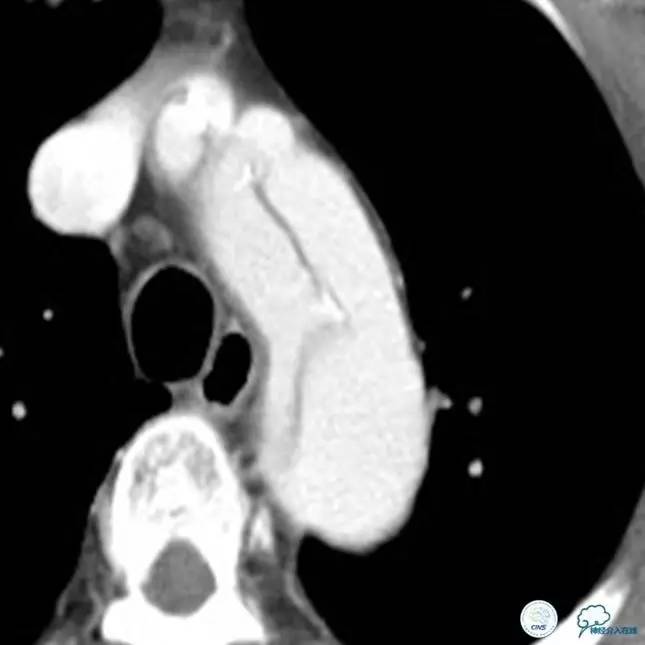

▼主动脉全程CT

中间诊断:

主动脉夹层 De Bakey Ⅰ型

脑梗死

治疗原则:

继续监测血流动力学指标

绝对卧床、控制血压、强效镇静与镇痛

急请血管外科会诊